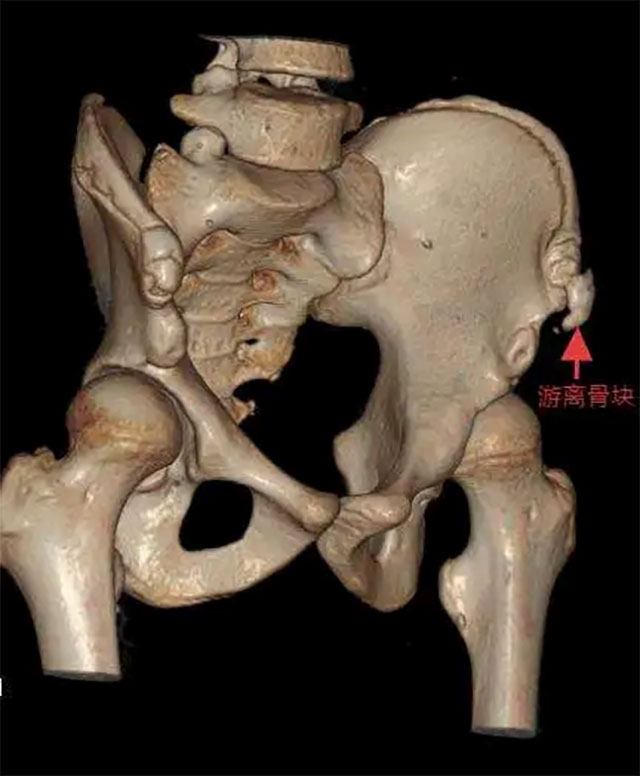

14岁的短跑主力小张,在校运会起跑训练中猛地蹬地发力,左髋部瞬间传来“撕裂般”剧痛,当场瘫坐跑道,冷汗浸透运动服。检查显示,他的左髂前上棘撕脱骨折,骨折块移位达3cm,正是起跑时肌肉的猛烈收缩牵拉导致了损伤。

针对青少年生理特点与运动需求,科室制定个性化治疗方案。对于骨折移位超1cm、关节功能受限或运动需求高的患者,优先采用微创切开复位内固定术——仅2-3cm的微创切口,沿髂嵴精准切开避开神经,最大程度减少组织损伤,再根据骨折情况用空心螺钉等方式坚强固定。